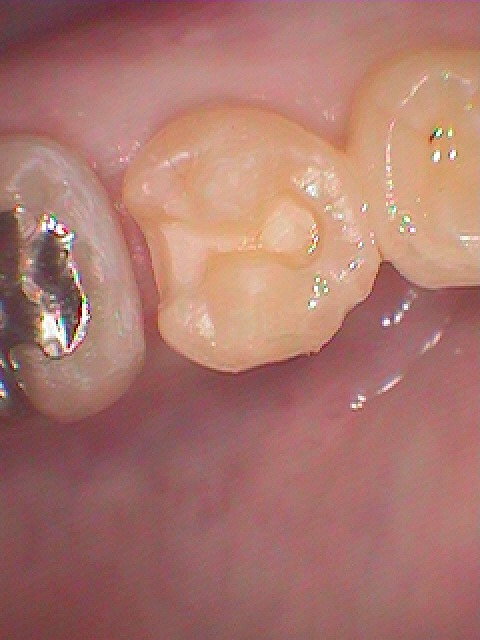

右下の5番部の虫歯治療 よく物が詰まるので診てほしい 30代男性

遠心隣接部が虫歯のため穴が開いていました

悪いところを除去し、CR樹脂にて覆罩を行っています

セレックセラミックにて審美的にもきれいに仕上げています

本来の歯のようにきれいに仕上がりました